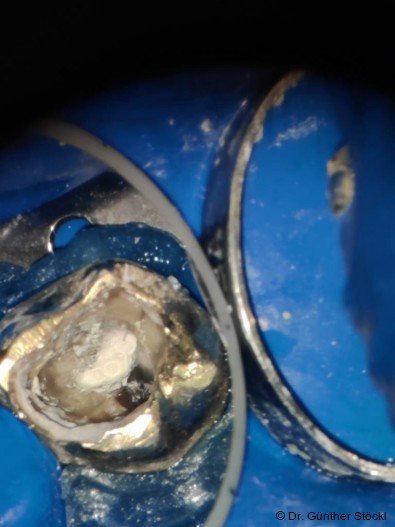

Foto: Dr. Günther Stöckl

Die Funktion des Wurzelkanalsealers besteht darin, die Hohlräume zwischen dem Kernfüllmaterial und den Dentinwänden zu füllen und eine dichte Verbindung herzustellen.14 Insbesondere die Penetration des Sealers in die Dentin­tubuli und anatomische Komplexitäten des Kanalsystems ist für eine suffiziente Versiegelung von entscheidender Bedeutung. Zu den Anforderungen zählen eine exzellente Versiegelungsfähigkeit, dimensionale Stabilität, Biokompatibilität, Unlöslichkeit gegenüber Gewebsflüssigkeiten, eine gute Adhäsion an den Kanalwänden sowie eine adäquate Verarbeitungszeit und einfache Handhabung.9, 10

Die Limitierungen von MTAs motivierten die Weiterentwicklung von Materialien, die auf dem Kalziumsilikat-Prinzip basieren, aber verbesserte Eigenschaften aufweisen.17 Die ersten speziell als Wurzelkanalsealer konzipierten Kalzium­­silikat-­zemente wurden im Jahr 2007 vorgestellt. Diese Materialien, zusammenfassend als Biokeramiken bezeichnet, werden nach ihrer Interaktion mit dem Gewebe als bioinert, biokompatibel oder bioaktiv klassifiziert.9 Moderne biokeramische Formulierungen basieren auf Kalziumsilikaten, Kalziumphosphat und Kalziumhydroxid, wobei als Röntgenkontrastmittel häufig Zirkoniumoxid anstelle von Bismutoxid verwendet wird, um Verfärbungen zu vermeiden. Ihr wesent­licher Vorteil ist die Bioaktivität: Bei Kontakt mit Gewebs­flüssig­keiten initiieren sie die Bildung von Hydroxylapatit, was zu einer chemischen Anbindung an die Dentinstruktur führt.17 Zudem schaffen sie durch die Freisetzung von Kalziumionen und Hydroxidionen ein hochalkalisches Milieu, das den periapikalen Heilungsprozess begünstigt.9 Diese Weiterentwicklungen führten zur Verfügbarkeit verschiedener Konsistenzen, darunter fließfähige Sealer und formbare Putty-Materialien für spezielle Repa­ratur­indika­tionen. Insbesondere die hydrau­lischen Kalziumsilikat-Sealer haben zudem vereinfachte Obturationstechniken, z. B. die Single-Cone-Methode, wieder in den Fokus der klinischen Anwendung gerückt.10

Die Partikelgröße des Zements beeinflusst die Abbindekinetik maß­geblich; kleinere Partikel vergrößern die reaktive Oberfläche, was die Hydratation beschleunigt und die Abbindezeit verkürzt. Gleichzeitig verbessert eine feine Par­tikel­vertei­lung die Penetration des Sealers in mikroanatomische Strukturen wie die Dentin­tubuli, was für einen hermetischen Verschluss essenziell ist. Studien belegen, dass biokeramische Sealer (z. B. Komet BioSeal) eine signifikant tiefere Penetration in die Dentin­tubuli erreichen als der Goldstandard AH Plus.17 Moderne, vorangemischte Formulierungen bieten zudem gegenüber MTA eine deutlich verkürzte Abbindezeit und eine erheblich vereinfachte Handhabung, was die klinische Effizienz und Standardisierung verbessert.17, 1 Ein idealer Sealer sollte unlöslich in Gewebsflüssigkeiten sein, um die Integrität des apikalen Verschlusses dauerhaft zu sichern.9 Einige Studien berichten für bestimmte vorangemischte Biokeramiken über eine höhere initiale Löslichkeit im Vergleich zu den ISO-­Normen oder zu AH Plus.